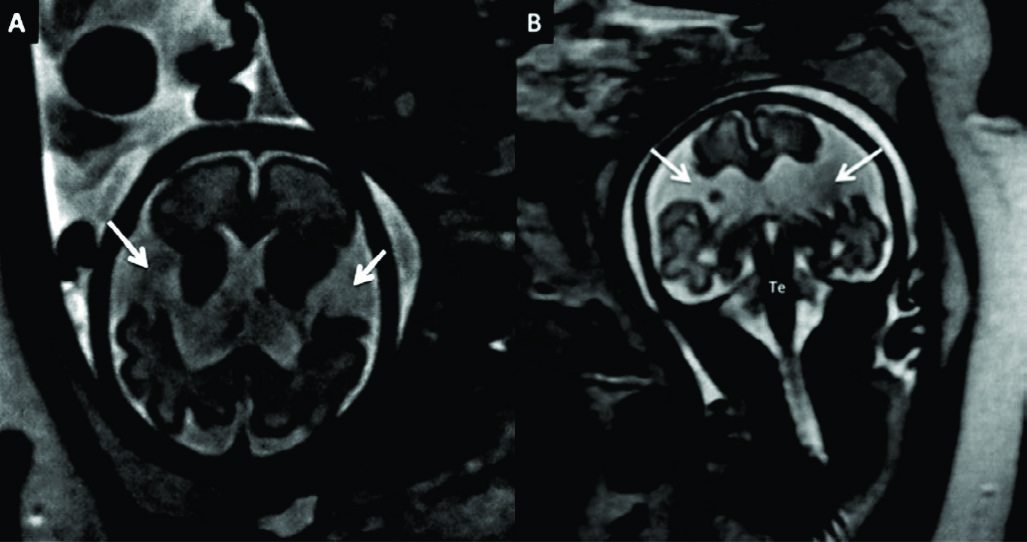

Figura 3

RM Fetal con Ventriculomegalia (Edad Gestacional: 28 semanas).

Imágenes seleccionadas de RMf en paciente referido por estudio ecográfico que muestra aumento del tamaño del sistema ventricular.

En A imagen en línea media donde se reconocen las estructuras normales: cuerpo calloso (CC), tronco encefálico (Te) y cerebelo (Ce) con su aspecto habitual.

En B el corte axial a nivel de los atrios ventriculares donde se evalúa el tamaño ventricular (16mm del lado izquierdo) y se reconocen la cisura inter-hemisférica completamente formada (CIE) y la cisura de Sylvio en la convexidad (CS).

En C y D cortes coronales que complementan la valoración anatómica. Luego del análisis preciso de todo el estudio no se encontraron otras anomalías asociadas.